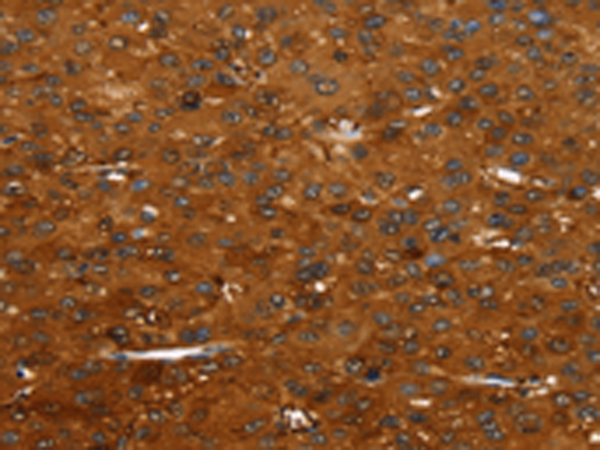

分类: 科研抗体货号: P10832别名: ALK-SMase应用: IHC反应种属: Human, Rat